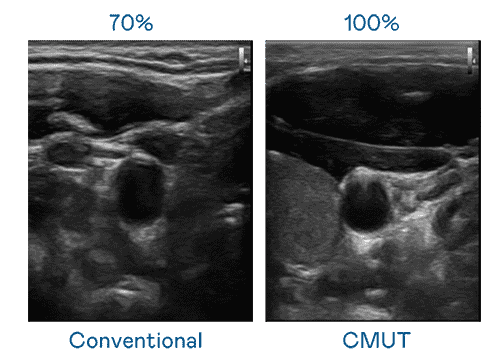

CMUT 技术是一种用电容式微机电元件来产生超音波讯号的技术。。。与传统 PZT 压电式技术相比,,,,CMUT 频宽增加 30%,,更宽频的超音波讯号让影像解析度大幅提升,,,是实现高影像品质医疗超音波扫描、、、促进精准医疗发展的关键技术。。。

大频宽带来超清晰影像

超音波影像的解析度高低,,首先取决于探头能发出的讯号频宽。。蓝狮在线 CMUT 可提供高清晰的超音波讯号,,提供高频宽、、、、高灵敏度、、、、影像纹理细节更高的超音波影像,,协助医护人员缩短影像判读时间及利用精准的医疗影像进行诊断。。。。